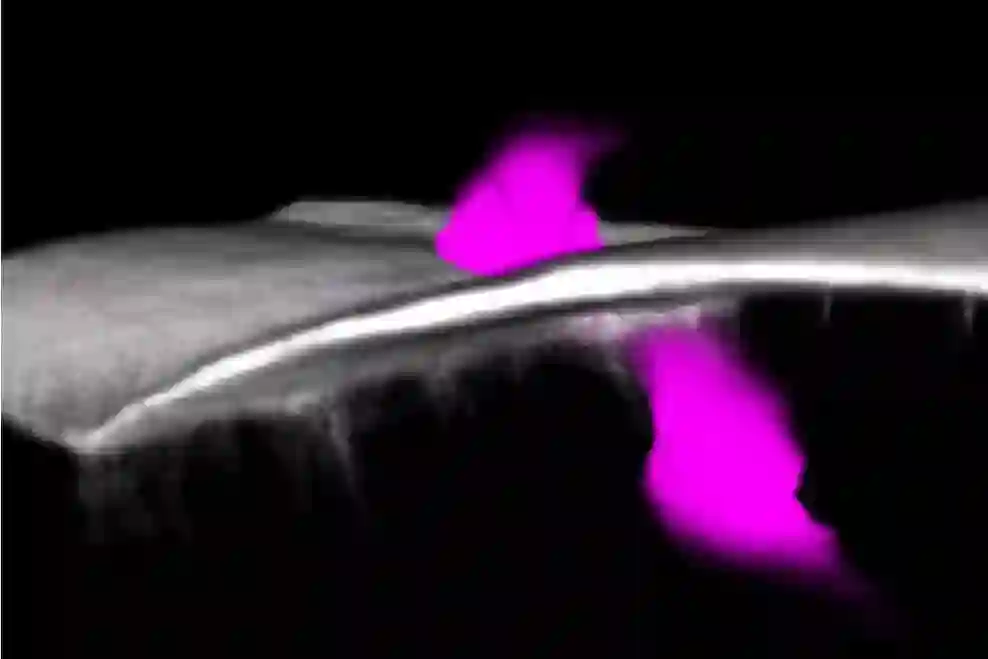

免疫细胞(洋红色)破坏基底膜以进入癌细胞。图片来源:布里斯托大学

为了进入癌细胞,免疫细胞需要首先破坏组织间的细胞外基质屏障层—基底膜区。研究人员观察到炎症细胞利用基底膜区的薄弱环节作为接近癌症的简便途径。那些离薄弱环节最近的癌细胞克隆往往会受到更多的炎症细胞的侵袭,因此它们生长得更快。

“这一癌症过程的‘新窗口’揭示了皮肤屏障层的‘弱点’,炎症细胞必须突破这一屏障层才能进入皮肤并吞噬癌细胞。现在我们知道了这些微穿孔的存在,我们可以将它们作为癌症疗法的靶标。”